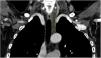

This is the case of a 66-year-old woman who presented to the dermatology office with a 6-month history of a lump on the left latero-cervical region without any accompanying symptoms. Her past medical story included thyroiditis and alfa-1 antitrypsin deficiency. The physical examination revealed the presence of a painless and non-inflamed 3cm nodule on the left latero-cervical region (Fig. 1). The neck ultrasound performed revealed the presence of a 3cm×2.1cm cyst with no peripheral or internal vascularity, which was consistent with a cyst (Fig. 2). The ultrasound-guided FNA and biochemical study of the content revealed the presence of elevated triglyceride levels (438mg/dL; normal range <150mg/dL), with normal cholesterol levels (82mg/dL; normal range <200mg/dL). To rule out any organic or treatable disease, a thoracic CAT scan was performed (Fig. 3).

Imaging modalities like ultrasonography, computerized tomography, and magnetic resonance imaging help us achieve the diagnosis and trim down some of de differential diagnosis. Cystic lesions are characterized by a well-demarcated round or oval with lack of nodularity, septations, or contrast enhancement. The most important Imaging modality for diagnostic purposes is the ultrasound-guided fine needle aspiration (FNA) of the cystic mass. Fluid with lymphocyte predominance and very high levels of triglycerides and chylomicrons (fat content, 0.4–4%) are highly suspicious for lymphatic cyst.1,2,4 Lymphangiography is the “gold standard” regarding imaging modalities and the diagnosis of thoracic duct malformations. However, with the ease and availability of high-resolution imaging and FNA, lymphangiography is often not attempted.2